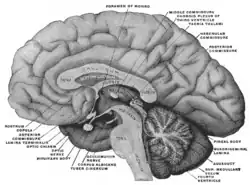

Mesal aspect of a brain sectioned in the median sagittal plane Pituitary

Pituitary Pituitary gland